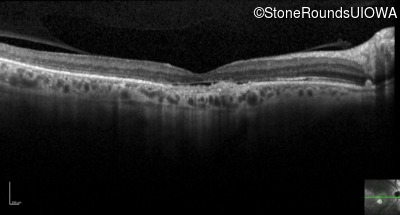

Optical Coherence Tomography - Right - 20/100

Exemplar / OCT Stack

OCT Stack